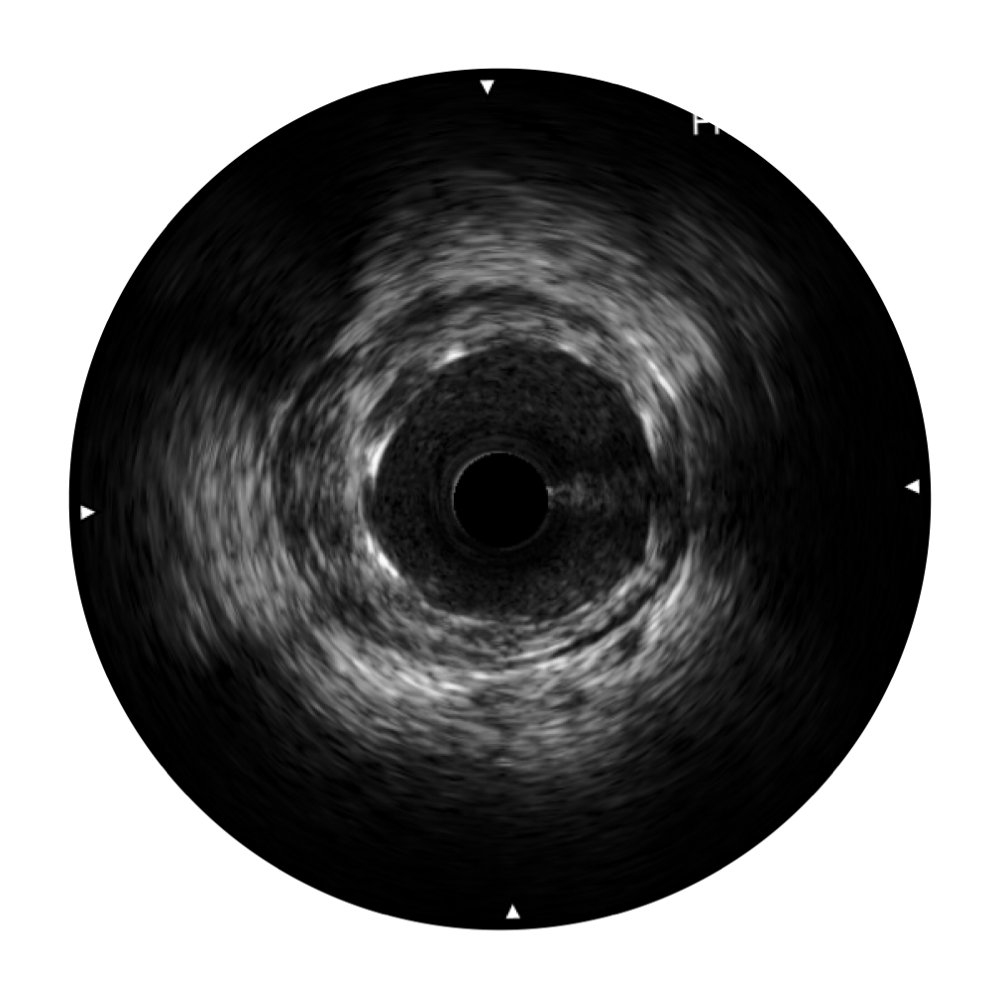

传统IVUS图像

对比传统IVUS导管成像,诸侯快讯官网宽频IVUS图像的近场支架梁显影更细腻,远场中膜外血管仍清晰可辨,兼顾远中近,兼顾分辨力与穿透深度